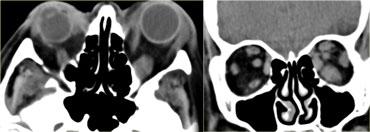

Bên trái là hình ảnh CT không tiêm thuốc cản quang của một bệnh nhân có áp xe màng xương hoặc áp xe quanh hốc mắt rõ ràng do biến chứng của viêm xoang sàng.

Điểm cần lưu ý như sau:

Không cần chờ có viền ngấm thuốc ngoại vi mới chẩn đoán áp xe!

Ở các vị trí khác, chúng ta thường chờ có viền ngấm thuốc rõ ràng mới chẩn đoán áp xe, nếu không có thì gọi là viêm mô tế bào (phlegmone).

Điều trị là điều trị viêm xoang.Đây là hình ảnh MRI của một bé trai 11 tuổi, có biểu hiện kích thích mắt phải vào tối hôm trước và thức dậy với tình trạng lồi mắt.

Hình ảnh chuỗi xung T1W có tiêm thuốc tương phản từ kết hợp kỹ thuật xóa mỡ (fatsat) thể hiện rõ ràng áp xe quanh hốc mắt là nguyên nhân gây lồi mắt.

Lưu ý hình ảnh viêm xoang sàng.

Điểm quan trọng tiếp theo cần lưu ý là:

Ở trẻ em, cần hết sức thận trọng với sự lan rộng ra ngoài xoang!

Bất kỳ thay đổi nào bên ngoài xoang đều nên được chẩn đoán là áp xe.

Ở trẻ em, màng xương quanh hốc mắt có nhiều lỗ thông hơn và bệnh sẽ dễ dàng lan rộng.

Vì vậy, hãy mạnh dạn chẩn đoán áp xe ngay cả khi chỉ có những bất thường nhỏ.Áp xe quanh hốc mắt có thể dẫn đến huyết khối tĩnh mạch mắt trên và dưới.